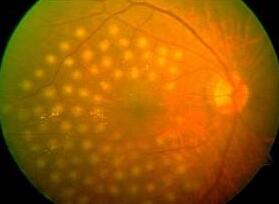

中渗